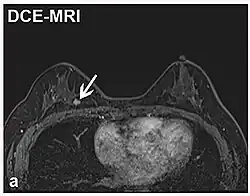

Realce de contraste dinâmico DCE Medidas de mudanças ao longo do tempo no encurtamento da relaxação spin-lattice (T1) induzido por um bolo de contraste de gadolínio.[85] O aumento rápido do contraste de gadolínio, juntamente com outras características, sugere malignidade.[86]